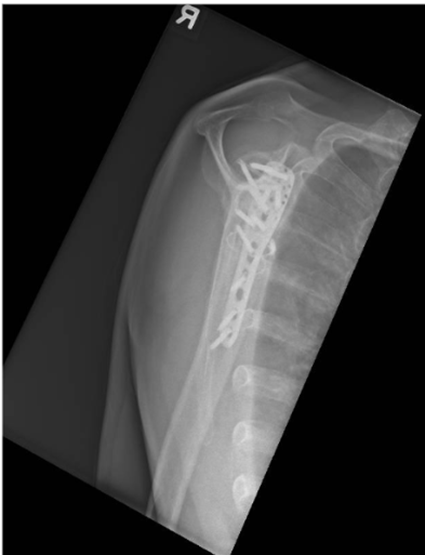

Image 5: 24-month follow-up radiograph of the right shoulder demonstrating bony union.

A. Anteroposterior (AP) view

B. Valpeau view

C. Lateral/ Y scapula view